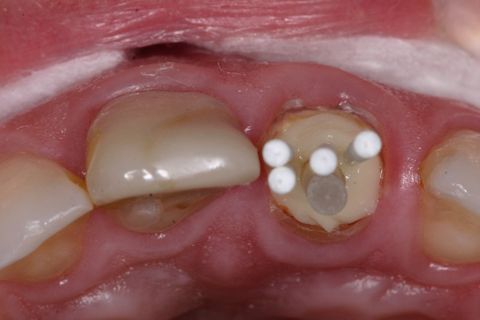

Inserção da resina no remanescente dentário

Inserção dos pinos acessórios na resina

Isolou-se o conduto radicular com óleo mineral e inseriu-se a resina composta (Fill Magic NT Premium, Coltene-Vigodent, Brasil) sobre o remanescente dentário com auxílio de uma espátula suprafill #1/2 (Figuras 5 e 6). Após o preenchimento do conduto com resina, foi inserido o pino Exacto cônico e os pinos acessórios previamente silanizados (Silano, Angelus, Brasil) e com a aplicação do adesivo (Fusion Duralink, Angelus, Brasil) (Figuras 7, 8 e 9). Em seguida, promoveu-se a fotoativação inicial do conjunto pino-resina por 20 segundos.